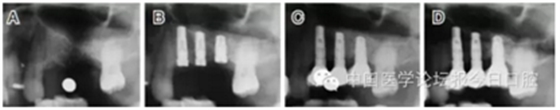

臨床上,可使用曲面體層放射線法及CT掃描方法對上額竇及可用骨量進行評估。其中曲面體層放射線法可提供多數(shù)病例的硬腭致密影像,為治療計劃提供有價值的參考(圖1);而使用CT掃描可提供骨密度信息。如骨高度、密度、牙槽嵴的方向位置,皮質(zhì)骨和松質(zhì)骨的特點,上頜竇黏膜厚度,病理狀態(tài)等。顯然,在上頜竇底提升術(shù)中,CT掃描影像的信息對于手術(shù)設(shè)計和減少治療風險非常重要。

圖1 采用曲面體層放射線法評估